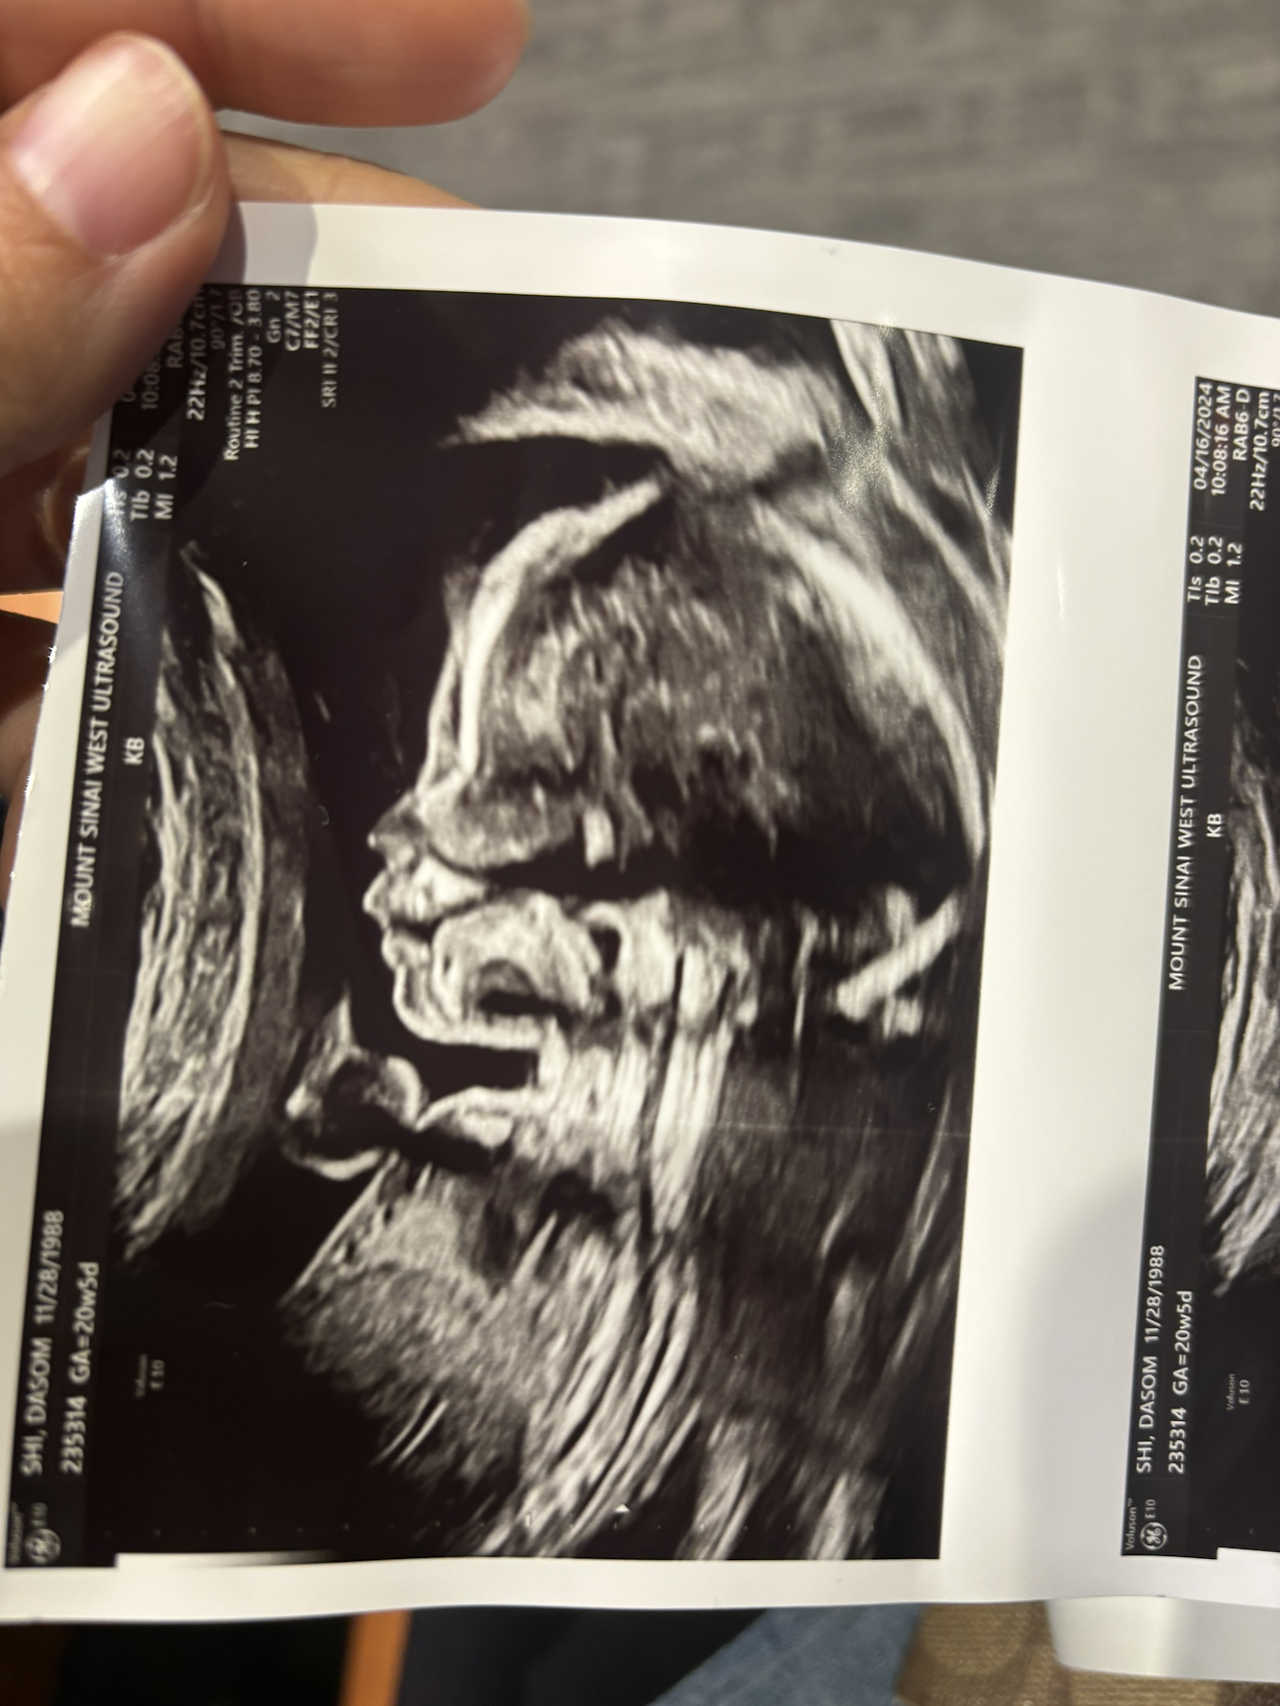

남편과 산부인과 입체 초음파 진료를 다녀왔다. 오늘 진료는 오래 걸리기도 해서 평소대로 혼자 갈까 하다가, 남편도 가끔은 같이 가는 게 좋겠다 싶어서 같이 가자고 했다.

이 와중에 애는 남편 판박이… 남편의 특징이 그대로 있다